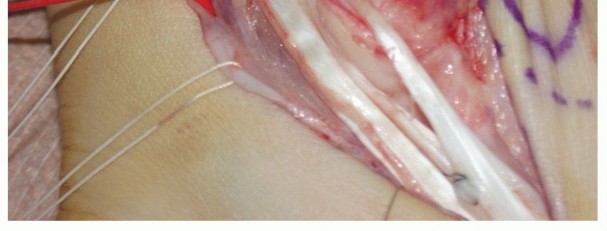

| Carry the incision down to the level of the peroneal tendon sheath (TECH FIG 1A). | |||

TECH FIG 1 • A. Intraoperative photograph of a left ankle (lateral approach) shows the peroneal tendons subluxing anteriorly (brevis is the gray arrowhead , longus is the white arrowhead , SPR is the black arrow). B. The peroneal tendons have been retracted anteriorly by the Penrose drain. Elevation of an anterior-based periosteal flap (outlined by dots) from the fibular groove has been completed. The black arrow shows the remnant of the SPR posteriorly. C. The tendons are relocated, after a groove-deepening procedure, into the recreated groove. The white dots outline the anteriorly based periosteal flap. It is then brought over to the posterior remnant of the SPR (black arrow). D. The flap is sutured to the remnant SPR with nonabsorbable sutures, completing the superior peroneal retinaculoplasty. |

| Make an incision in the peroneal sheath along the posterior border of the fibula. Retract the peroneal tendons anteriorly (TECH FIG 1B). | |||

| We routinely reinforce the SPR with a soft tissue periosteal flap elevated from the fibular groove from a posterior to anterior direction. | |||

| Raise the periosteal flap, measuring about 1.0 × 3.0 cm, sharply, from posterior to anterior. After the flap is | |||

| Reduce the peroneal tendons and use the periosteal flap to contain the tendons, with the visceral side of the periosteum facing the tendons (TECH FIG 1C). | |||

| Suture the flap to the posterior remnant of the SPR with a series of 3-0 polybraided nonabsorbable sutures (TECH FIG 1D). | |||